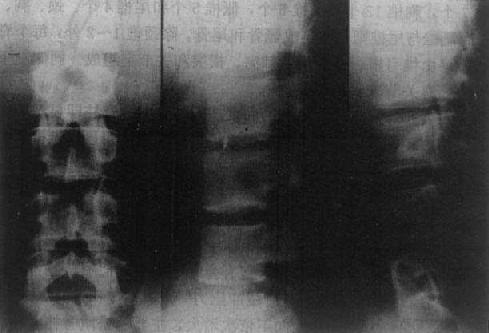

在正位片上,椎体呈长方形,从上向下依次增大,主要由松质骨构成,纵行骨小梁比横行骨小梁明显,周围为一层致密的骨皮质,密度均匀,轮廓光滑。椎体两侧有横突影。在横突内侧可见椭圆形环状致密影,为椎弓根横断面影像,称椎弓环。在椎弓根的上下方为上下关节突的影像。椎弓板由椎弓由椎弓向后内延续,于中线联合成棘突,投影于椎体中央的偏下方,呈尖向上类三角形的线状致密影,大小与形状不同(图2-1-5、6)。

在侧位片上,椎体也呈长方形,其上下缘与后缘成直角。椎弓居其后方。在椎体后方的椎管显示为纵行的半透明区。椎弓板位于椎弓根与棘突之间。棘突在上胸段斜向后下方,不易观察,于腰段则向后突,易于显示。上下节突分别起于椎弓根与弓板连接之上、下方,下关节突在下个脊椎上关节突的后方,以保持脊椎的稳定,不向前滑。脊椎小关节间隙匀称的半透明影。颈、胸椎小关节侧位清楚,腰椎正位清楚。椎间盘的纤维软骨板、髓核及周围的纤维环系软组织密度,故呈宽度匀称的横行半透明影,称之为椎间隙(intervertebral space)。椎间孔居相邻椎弓、椎体、关节突及椎间盘之间,呈半透明影,颈椎斜位显示清楚,胸、腰椎侧位清楚,呈类圆形(图2-1-5、6)。

图2-1-5 正常腰椎正侧位

图2-1-6 正常腰椎(正位、侧位、斜位)